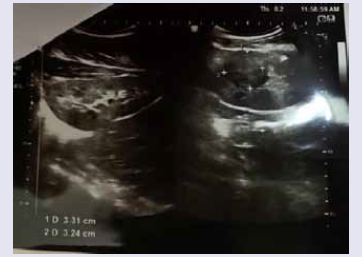

of Brain [Figure 5], fundoscopy was normal. Ultrasonography of

the whole abdomen revealed a small focal lesion in the left kidney

[Figure 6]. Other tests like hemoglobin, complete blood count,

along with small focal lesion in left kidney in ultrasonography of

abdomen are the positive imaging findings in our case.[8] The 18-yearold